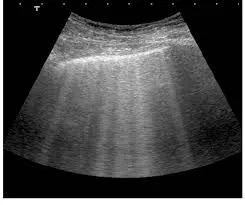

Doppler da FAV: O exame Doppler revelou um fluxo sanguíneo elevado através da fístula AV, caracterizado

por um padrão de onda contínuo com alta velocidade de fluxo (2130mL/min). Não foram identificadas estenoses significativas ou sinais de trombose na fístula. Observou-se uma dilatação significativa da veia eferente, indicativo de fluxo cronicamente elevado.